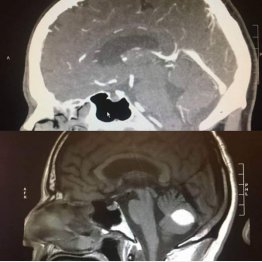

脳腫瘍が手術前に消えた…説明不能の現象に「奇跡だ!」

どうしてこんなことが起きたのか……米カリフォルニア大サンフランシスコ校(UCSF)の外科医らが頭を抱えている“医療ミステリー”が話題だ。

CBSサクラメント(11月13日付電子版)などによると、カリフォルニア州ローダイに住むポール・ウッドさんは今年7月、激しい頭痛と共に…